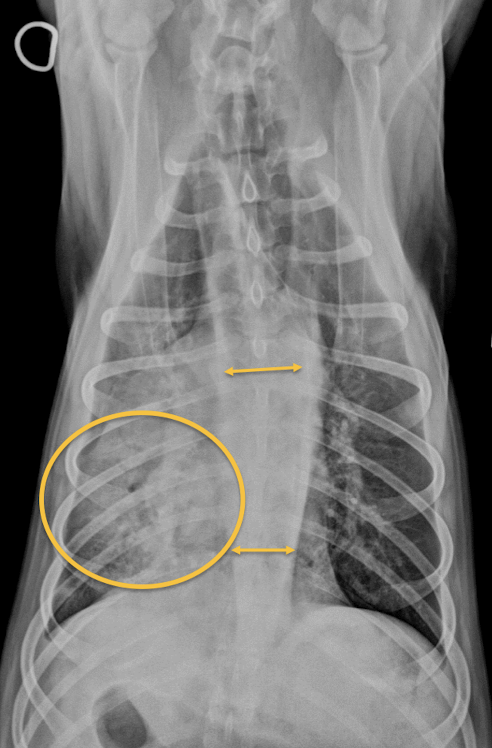

13

Juvenile idiopathic megaesophagus